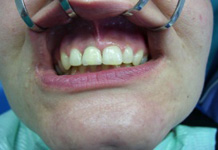

Náhrada jednoho zubu

Klasickým příkladem a indikací pro použití implantátu je ztráta jednoho zubu (v tomto případě v předním – frontálním úseku) v jinak zdravém, nepoškozeném chrupu.

Nejčastější příčinou takové ztráty je sportovní nebo dopravní úraz.

Náhrada jednoho zubu pomocí implantátu je možná také v postranním úseku chrupu. Při ztrátě většího počtu zubů ve frontálním nebo postranním úseku může být mezer uzavřena větším počtem jednotlivých implantátů.

Při ošetření pomocí jednotlivých implantátů zůstávají sousední zuby neporušené – intaktní. Při klasickém ošetření pomocí můstků musejí být tyto zuby obroušeny!